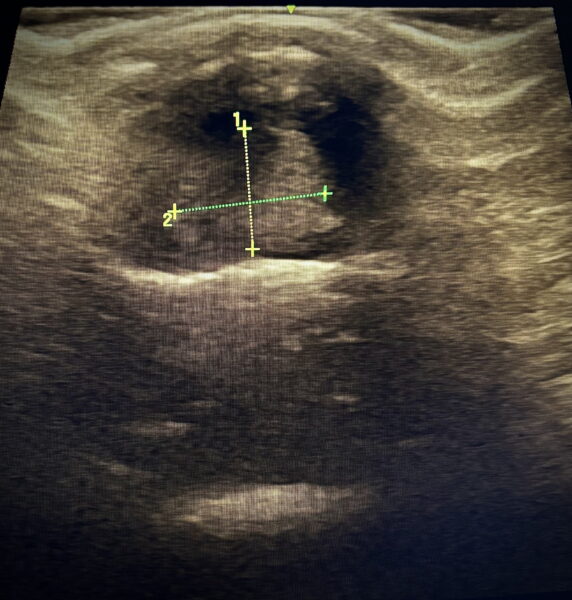

Foto. archiwum prywatne. Guz przysadki u szczura